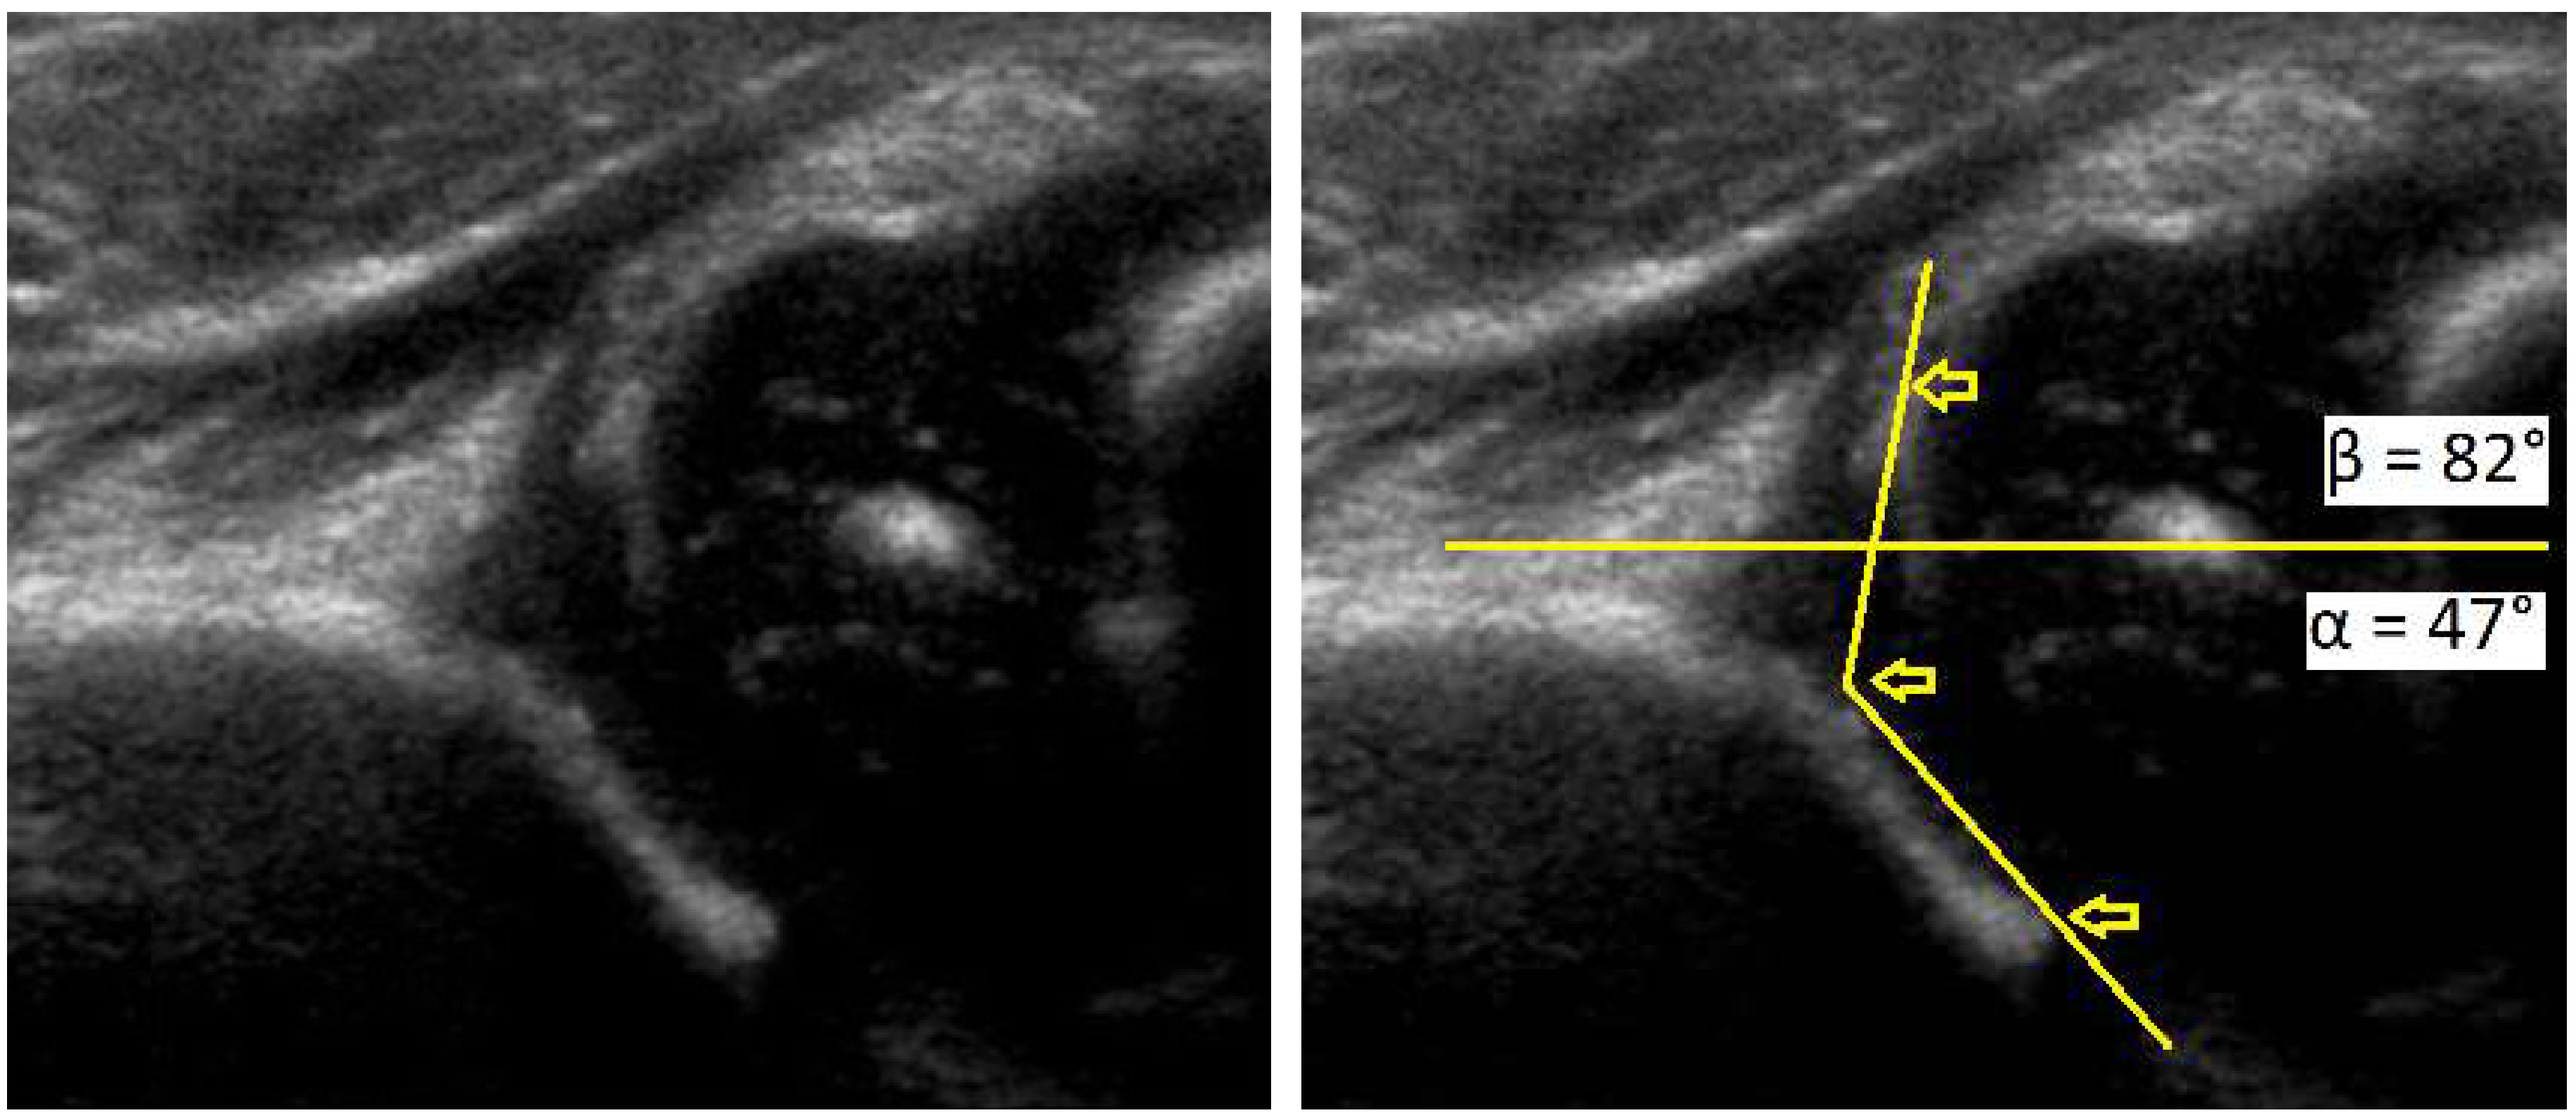

Figure 1.

Development dysplasia of the hip (DDH)-ultrasound. In Graf’s classification type D (Decentring hip): Bony roof is severely deficient, bony rim is rounded to flattened, cartilage roof is displaced, α angle is 43–49 ° and β angle >77 °.